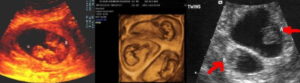

Узи двойни при беременности: фото на ранних сроках в 5-6 недель и позже

Определение двойняшек и близнецов осуществляется таким продуктивным методом исследования, как УЗИ. Этот вид обследования обеспечивает информацией о месте расположения ребенка, имеется ли многоплодная беременность и др.

Как правило, двое эмбрионов четко определяют на УЗИ с самых ранних недель — 5-7. Позже врач способен это определить и без применения ультразвуковой диагностики. Двойняшек можно выявить по такому признаку, как увеличенный размер матки, уже с ранних сроков, а медицинская диагностика с применением ультразвука покажет двух детей только на 1 скрининге — в 10-14 недель.

Двойняшки покажутся на УЗИ уже с 5 недели

Следовательно, наличие двойняшек в утробе выявляется посредством ультразвука уже через месяц после зачатия, на снимке они выглядят как 2 образования темного цвета внутри полости матки (см. фото УЗИ-обследования двойни ниже).

- УЗИ-диагностика двойни через 11 недель показывает немного уменьшенные для своего срока развития размеры первого и второго плода – примерно 4,2-4,8 см.

- При обследовании на 12 неделе эмбрионы имеют длину по 6 см, а их вес составляет примерно 8 грамм.

- На 20 неделе малыши имеют вес 350 грамм. Можно заметить, что один ребенок крупнее второго. Это происходит из-за кровяного шунта, по которому происходит постоянный сброс крови одному из двух плодов.

- После 32-34 недель малыши набирают вес до 2 кг.

Увидеть двойню на УЗИ при беременности можно уже через месяц после зачатия. В этом случае специалист отметит на экране монитора два пятна черного цвета, которые хорошо просматриваются ультразвуком